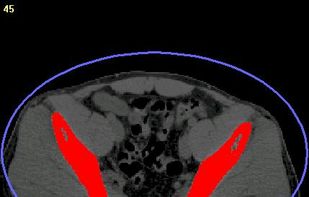

MedSeg is described as 'Online tool for AI-enhanced medical image segmentation of radiological images (CT and MRI). Works with DICOM and NIfTI using Chrome' and is an website. There are four alternatives to MedSeg, not only websites but also apps for Windows, Linux and Mac. The best MedSeg alternative is 3D Slicer, which is both free and Open Source. Other great sites and apps similar to MedSeg are AMIDE, InVesalius 3 and 3D-DOCTOR.